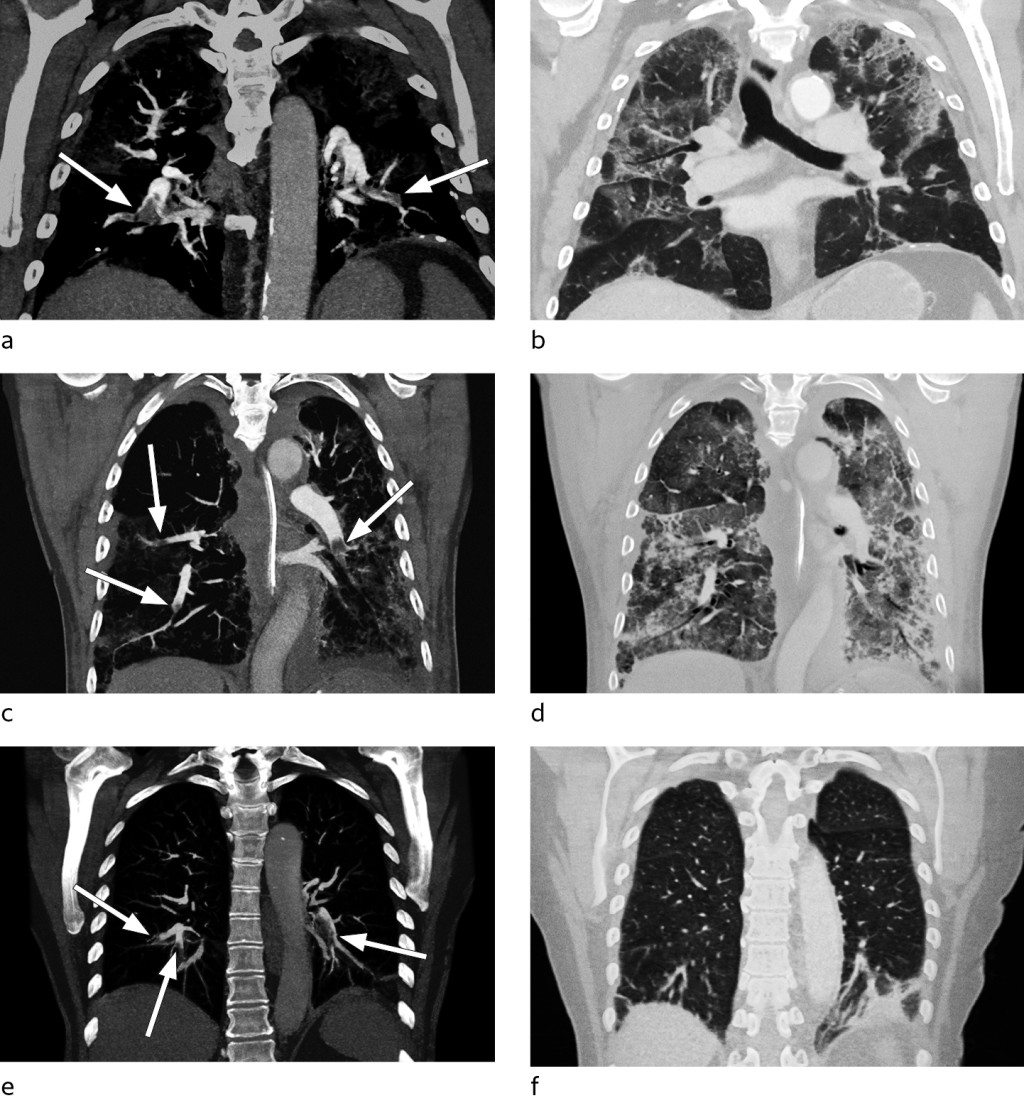

From day 9, the patient showed increasing oxygen demand, and required 10 l/min via a non-rebreathing mask to maintain SpO2 > 94 %. He was gradually becoming increasingly tired and weak. A chest X-ray on day 12 showed the lung opacities to be largely unchanged. Owing to a lack of improvement in oxygenation and a strong and sustained increase in D-dimer levels to > 10 mg/ml (Figure 1), CT pulmonary angiography was performed on day 15. This revealed bilateral segmental and subsegmental pulmonary embolisms, in addition to widespread infection-related opacities (Figures 2a–b). After initiation of anticoagulation therapy (enoxaparin 100 mg × 2), the patient's oxygen demand slowly decreased and his general condition rapidly improved.

Based on reports of increased incidence of venous thromboembolism in intensive care patients with COVID-19, we decided to increase the prophylactic dose of enoxaparin to 40 mg × 2. On day 7, the patient's D-dimer levels increased from 2.8 to 24 mg/l. His ferritin level was > 2 000 µg/ml and treatment with an interleukin-1 receptor antagonist (anakinra) was initiated on day 10. Radiological progression of the pulmonary opacities was seen up to day 13, while D-dimer levels decreased after initiation of anakinra (Figure 1). However, owing to a renewed increase in D-dimer from 16 mg/ml to 26 mg/ml, CT pulmonary angiography was performed on day 16. This revealed bilateral peripheral pulmonary embolisms and widespread opacities in all lobes (Figures 2c–d). Anticoagulation therapy (enoxaparin 100 mg × 2) was initiated, but after a long disease course with severe respiratory failure that did not improve, the patient died on day 22.

A previously healthy woman in her seventies experienced a week of illness with mild dry cough and upper respiratory tract symptoms. SARS-CoV-2 was detected in bronchial secretions after two days. After being free of symptoms for two weeks, the patient again developed a dry cough and was hospitalised 23 days after symptom onset, with activity-related dyspnoea and tachypnoea. Upon admission, she had respiratory alkalosis and a D-dimer level of 1.9 mg/ml. Chest X-ray was normal. CT pulmonary angiography was performed, and revealed bilateral segmental and subsegmental pulmonary embolisms affecting all lobes, but no opacities suggestive of infection (Figures 2e–f). She received oral anticoagulant therapy (apixaban 10 mg × 2) and was discharged when she showed improvement.